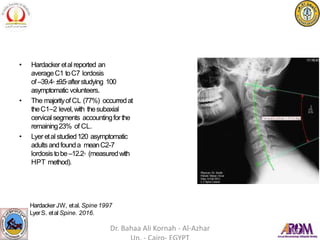

• Hardacker etal reported an

averageC1 toC7 lordosis

of–39.4◦±9.5◦afterstudying 100

asymptomatic volunteers.

• The majorityofCL (77%) occurredat

theC1–2 level,with thesubaxial

cervical segments accountingforthe

remaining23% of CL.

• Lyer etal studied120 asymptomatic

adultsandfounda meanC2-7

lordosistobe–12.2◦ (measuredwith

HPT method).

Hardacker JW, etal. Spine 1997

LyerS. etal Spine. 2016.